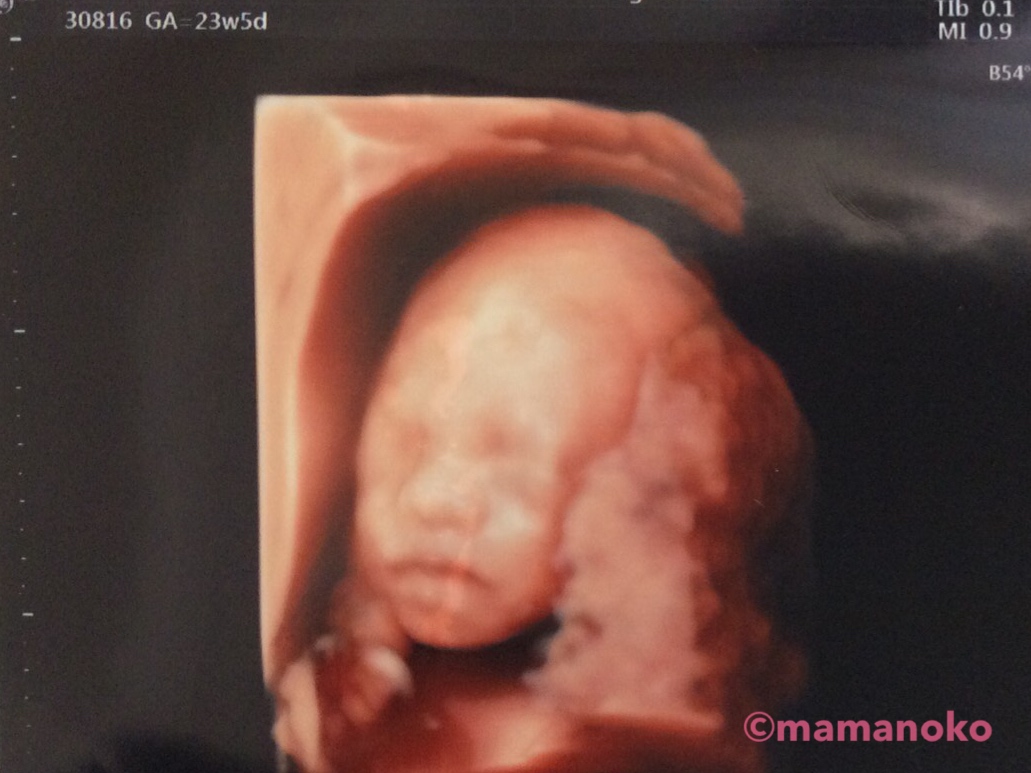

「エコーのままだ!」

こちらは、妊娠27週の3Dエコー画像と出産直後の写真です。ママは生まれてきた男の子を見て「鼻や髪の毛が3Dエコーのままだ!」と感動したそうですよ。